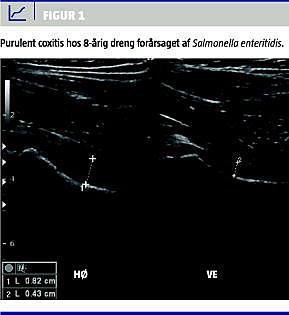

Ved ankomsten noteredes temperaturforhøjelsen, højresidige hoftesmerter med indskrænket bevægelighed samt C-reaktivt protein (CRP) 188 (ref. < 5) og leukocytter 21,9 (ref. 4,5-13,5). Ultralydsundersøgelse (UL) påviste ansamling i højre hofte (Figur 1 ). Leddet blev aspireret. Behandling blev initieret med ceftriaxon 3,7 gram intravenøst 1 og gentamycin 185 mg intravenøst 1.

Fra aspiratet blev der dyrket Salmonella enteritidis. Efter yderligere to døgn blev han atter aspireret efter UL-påvist ansamling i højre hofteled (Figur 1 ). Da den kliniske tilstand og infektionstallene forblev uændrede, blev der efter yderligere to døgn foretaget synovektomi med indlæggelse af gentamycin. Dyrkningssvaret Salmonella enteritidis medførte justering af antibiotikabehandlingen, således blev gentamycin erstattet med ciprofloxacin 750 mg peroralt 2.